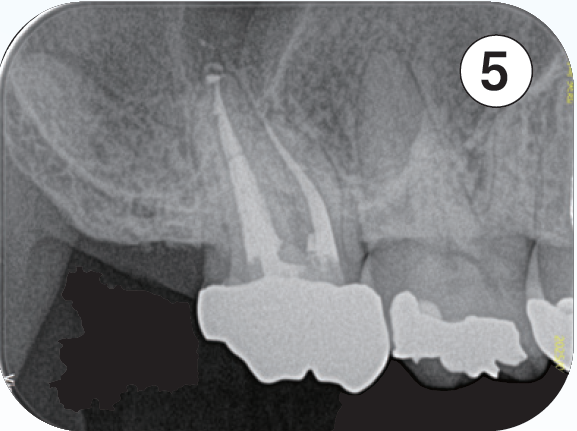

「臨床症例3」2022年9月16日に上顎前歯部腫脹と鈍痛を主訴に紹介元の歯科医院を受診

●年齢 40代 男性

難治性歯内療法疾患と診断を受け、当院を紹介される。同年10月19日当院を受診。問診時、10代の時に前歯部を強打し歯科医院を受診するも経過観察のまま放置していたとのことで、上顎左側中切歯の根尖部が外部吸収様の形態が確認でき、根尖孔もかなり開いていることが予測できた。CBCTでは唇側皮質骨は開窓し、根尖病変は中切歯、側切歯の根尖部を含む広範囲に広がっていることが確認できる。治療においては根尖孔のゲージングで#100とし、作業長の1ミリアンダーに止まるリーマー#120で抵抗形態を付与し、MTA製剤の根尖外への溢出を極力抑えるように努めて根尖部の閉鎖を行った。

その次に、上顎左側側切歯の感染根管処置を行った。側切歯は中切歯とは違い、狭窄が進行し穿通障害歯を呈していた。穿通し作業長を確認し、根管充填を行った。術後3ヶ月、1年の状態は治癒傾向が継続しており、臨床症状も無い。外科的アプローチを回避できる結果となった。

臨床症例3 その1

①初診時(2022/10/19)

左上1、2番の根尖部を含む大きさの根尖病変が認められる

左上1は根尖部は外部吸収が認められる

②左上1番 EMR時レントゲン像

根根尖孔径は#100に相当した

③MTA製剤を用いて根管充填を行なった

作業長1ミリアンダーに#120のリーマーにて抵抗形態を付与しMTA製剤が根尖外に多量に溢出しないように努めた

④根管口まではガッタパーチャとMTAシーラーを用いて充填した